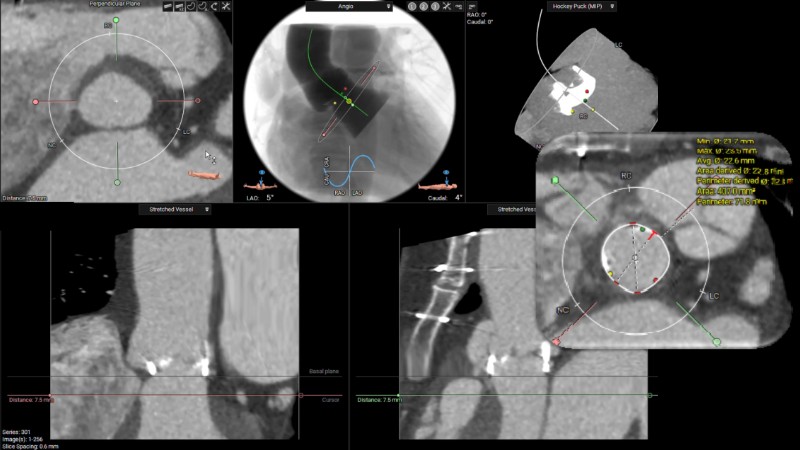

This session explores the evolving landscape of transcatheter aortic valve implantation (TAVI) with a focus on supra-annular valve technology. It covers techniques for achieving commissural alignment, considerations for small aortic annuli, and advantages in treating bicuspid aortic valve disease, supported by clinical data and illustrative cases.

- To learn about TAVI considerations when treating patients with a small aortic annulus - with a review of supporting clinical data